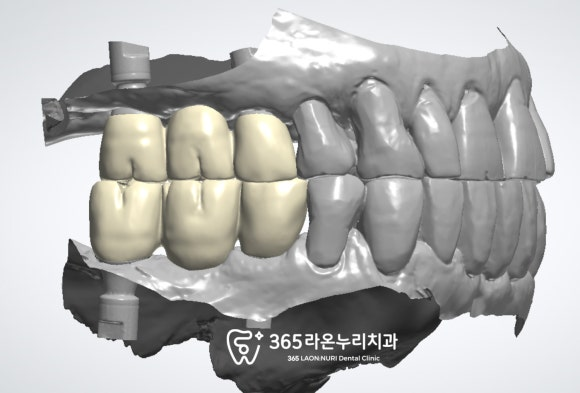

오른쪽 위아래 먼저 진행되고 있는 모습이며

이 과정에서

저희 남촌동 치과 의 강점인

임시치아를 제작해 드리기 위하여

디자인하고 있는 모습입니다.

이렇게 임시치아를 통해

빠르게 저작기능 회복이 가능합니다.

이렇게 어느 정도 고정력을 얻은

픽스처 위로 임시치아를 연결하게 되는데

이때 불편감이 있거나

걸리는 부분이 있다면

미리 보완할 수 있기에

최종 보철 장착 시,

더욱 안정적이고 편안하게

잘 만들어드릴 수 있겠죠?